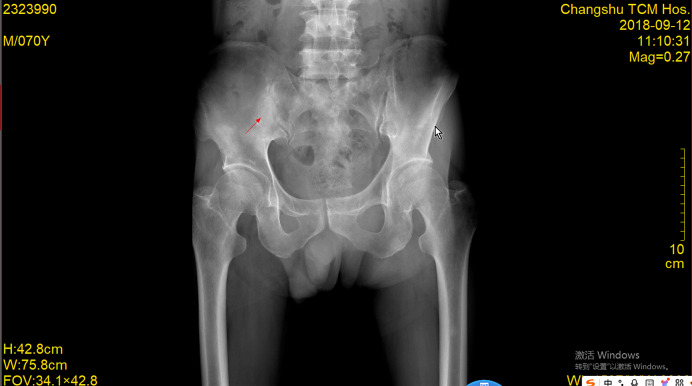

前列腺癌是男性最常见的恶性肿瘤之一,骨转移是常见的并发症,严重影响患者的生活质量和生存率。病例介绍:本文报道一例前列腺癌多发骨转移患者在化疗联合内分泌治疗后完全缓解并存活6年。结论:本文通过详细介绍患者的治疗过程及随访结果,探讨化疗联合内分泌治疗在前列腺癌骨转移治疗中的应用价值。

Case presentation: This article reports a case of a patient with multiple bone metastases from prostate cancer who achieved complete remission and survived for 6 years following chemotherapy combined with endocrine therapy.